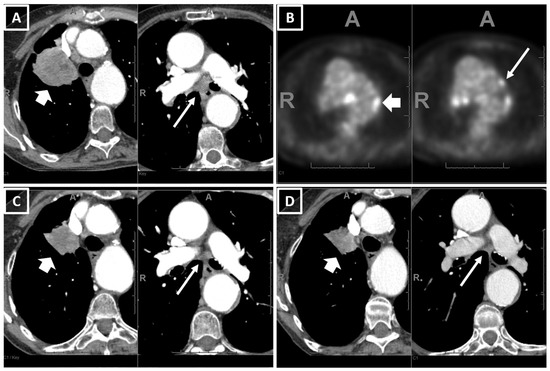

2.2. CT Scan Acquisition and Review

| On baseline CT: Number of patients with metastatic involvement in organs (n, col%) | |||||||

| On baseline CT: Target lung lesion size in mm5 [median, Q1–Q3] | |||||||

| 35.5 | 24–50 | 38 | 24.5–51.5 | 35 | 24–47 | 0.4821 | |

| On baseline CT: Number of involved organs with metastasis per patient [median, Q1–Q3] | |||||||

| 3 | 2–4 | 3 | 2–4 | 2 | 2–3 | 0.0015 * | |

| No. of involved organs on baseline CT | ||||||||

| 1.67 | [1.27 | 2.27] | 0.0004 | 1.59 | [1.19 | 2.20] | 0.0027 | |